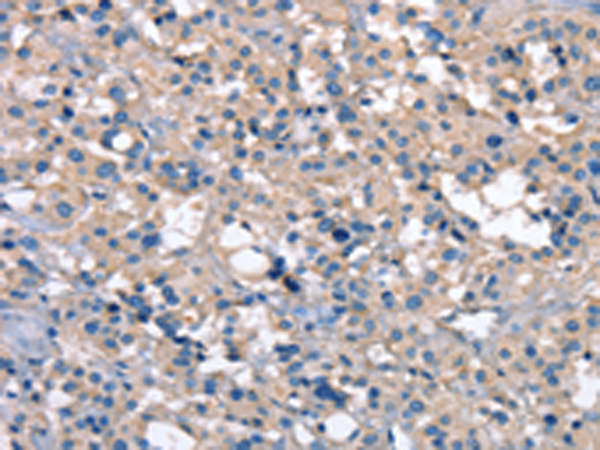

分类: 科研抗体货号: P03661别名: LIMK; LIMK-1应用: WB,IHC反应种属: Human, Mouse, Rat